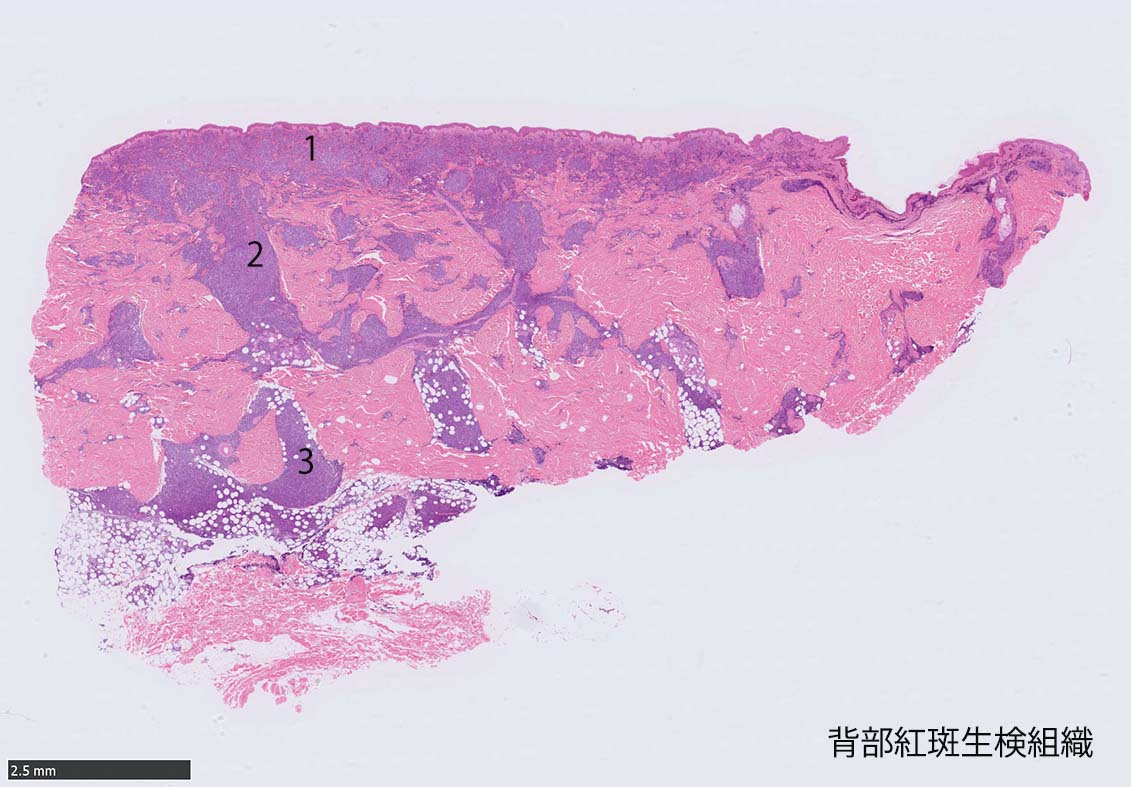

IWT-case: 4つの点で囲んだ紅斑から生検.

皮膚病変は64-100%の症例で認められ皮膚病変が契機となり診断されることも多い.

マクロ所見は多彩で, 孤在性から播種性の分布を呈し, 腫瘤, 局面, 紅斑いずれの形態もとりえる.

腫瘍細胞は真皮を主座として, 皮下脂肪織まで, びまん性かつ単調monotonousに増殖することが多く, 表皮向性はみられない. 本例では血管や付属器中心あるいは脂肪織内に結節状の浸潤増殖を示した.

本例皮膚真皮増殖細胞はCD4+, CD56+, CD123+, CD303+, lysozyme(-). がん研有明病院, Sakamoto K, Takeuchi K先生にconsultationを行い, TCF4, TCL1の陽性が確認された.(consultationを受けていただいた両先生に深謝いたします.)